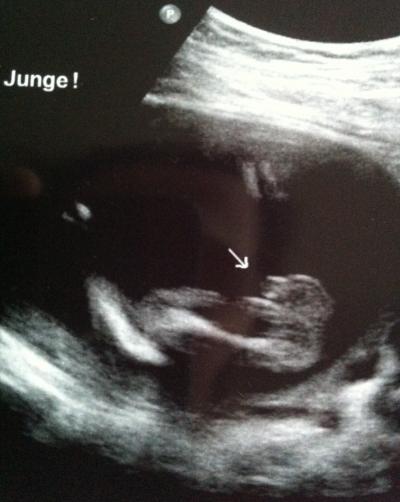

Soooo das erste was mein Arzt beim US sagte : Ooo es wird ein Junge zu 100 % :-))) Mein Mann konnte es nicht erkennen aber ich. Es ist alles in Ordnung. Das Baby ist 25 cm und 350gr schwer. Freu mich total. Allerdings hat er sich das Herz seehr lange angeschaut ( 5 Min etwa ). Mache mir deshalb sorgen, aber wenn was wäre hätte er es mir ja gesagt oder ??? Ps: Den ersten Strampler haben wir heute übrigens gekauft !!

Bild zu FA bericht + Outing :) - Forum für Juli - Mamis

Jo, des nenne ich mal ein eindeutiges Outing... da hat dein FA einen tollen Schnappschuss hinbekommen... Herzlichen Glückwunsch zum kleinen Jungen und es freut mich, dass es dem Kleinern gut geht und dass er so toll gewachsen ist... man schon 3 1/2 Tafeln Schoki schwer klasse !!! LG deine Keksi